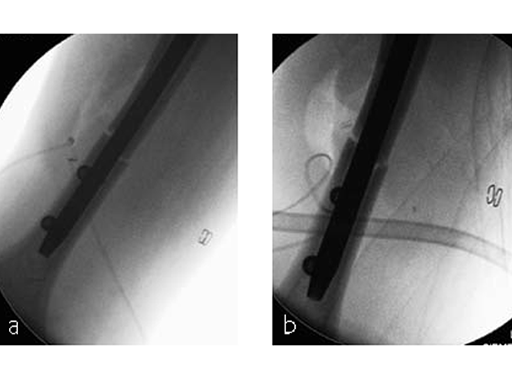

The patient was operated on in beach chair position. For the exploration of the radial nerve, a limited anterolateral approach was used. The nerve was mobilized and retracted laterally. An anterolateral approach to the proximal humerus was performed. The supraspinatus showed a small acute rupture without retraction. The supraspinatus tendon was split to get access to the insertion area on the humeral head. A 270 mm long MultiLoc Humeral Nail of 8.5 mm diameter was inserted under visual and x-ray control to the desired endpoint. Reduction of both the proximal and the distal humerus fracture was anatomical. In the lateral view there was a small gap, and it was decided to apply compression after distal locking (Fig 12). Proximally, three MultiLoc screws were inserted and a 2 mm end cap was placed. Finally, the supraspinatus rupture was reconstructed with transosseous sutures and secured with an augmentation plate. The posterior greater tuberosity fracture was secured with Fiber Wire to the MultiLoc screws. Fig 13 illustrates the definitive fixation.